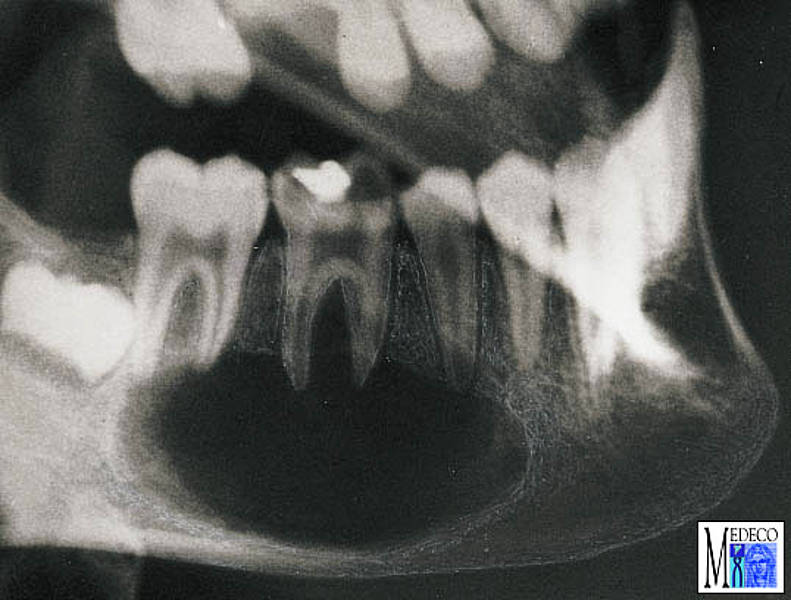

Раздел: Галерея впечатлений